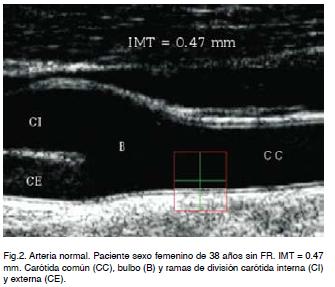

En la arteria carótida común normal el espesor de las capas interna y media (Íntima-Media) tiene valores inferiores al milímetro (Figura 2).

El incremento del espesor íntima-media es un indicador de enfermedad aterosclerótica. Para su evaluación se considera raza, edad y sexo. De acuerdo a diferentes estudios de grandes poblaciones se ha establecido la distribución de esta variable (espesor de íntima-media) según edad, sexo y raza tomándose el percentil como medida del porcentaje en que se divide la muestra.

Valores por encima del percentil 50 son considerados como positivos para el diagnóstico de aterosclerosis.